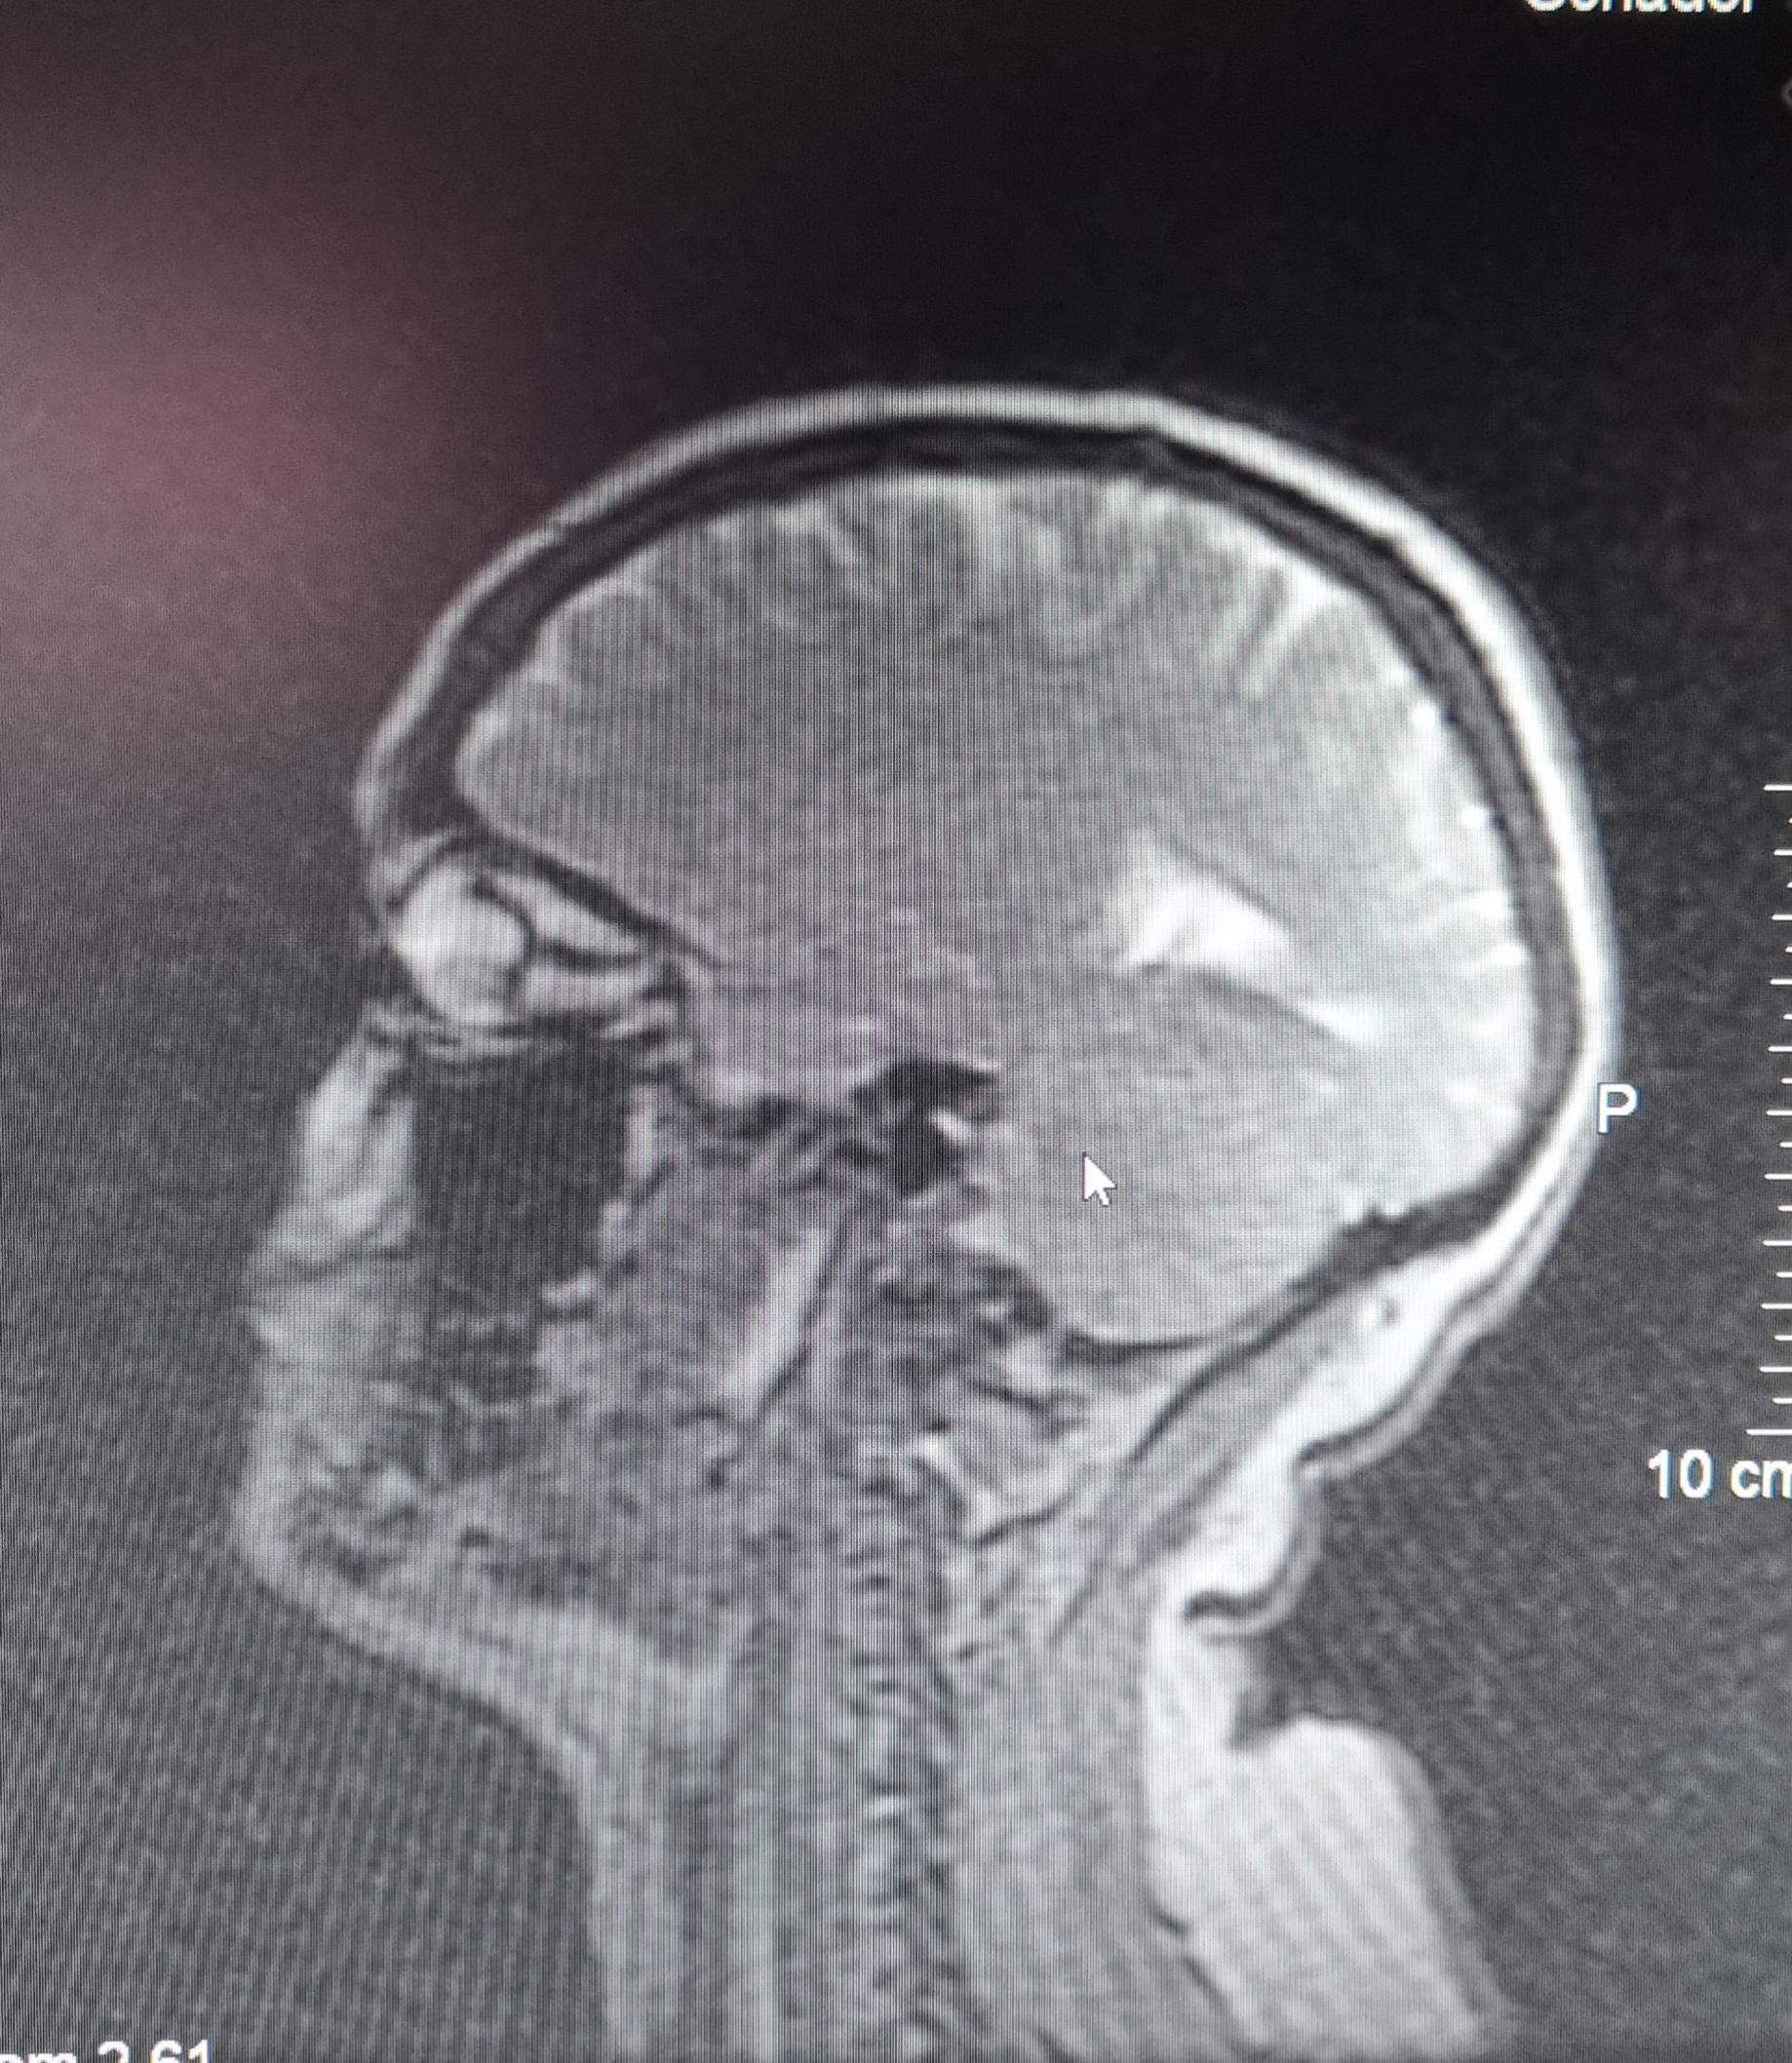

MRT Schädel? (Gesundheit und Medizin, Gehirn)

Das Schädel-Hirn-Trauma (SHT) ist eine physikalische Schädigung von Hirngewebe, die die Hirnfunktion vorübergehend oder dauerhaft einschränkt. Die Diagnose wird klinisch vermutet und durch bildgebende Verfahren, hauptsächlich Computertomographie (CT), bestätigt. Die erste Behandlung besteht aus einer zuverlässigen Sicherung der Atemwege.